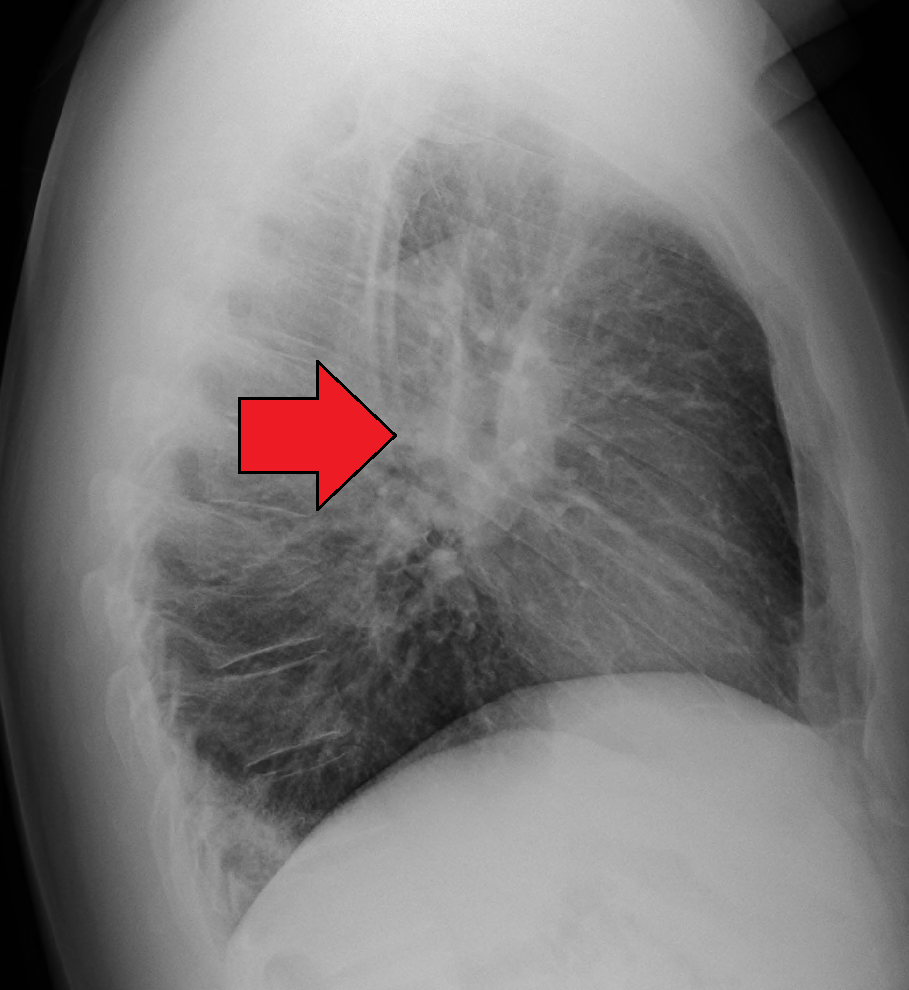

Fibrosis on lung CT shows subpleural patches, which progress to diffuse fibrosis and eventually forms a ‘honeycomb’ pattern which is an indicator of end-stage pulmonary fibrosis.

The granulomas mostly affect the hilar lymph nodes and lungs, causing restrictive lung disease.